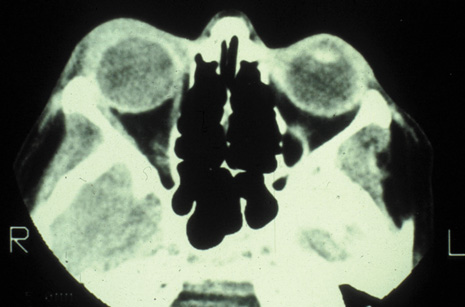

CT is particularly useful for imaging orbital and subperiosteal abscesses. Because the periorbit is not adherent to the orbital walls except at the suture lines, an abscess lifts the periorbit, creating a convexity in the orbital periosteum (Fig. 16). Usually subperiosteal abscess formation occurs adjacent to the involved sinus,25,64 but occasionally it occurs at a remote location such as the superolateral orbit.65 Gas may be found within a subperiosteal abscess or within the orbit, arising either from gas-forming bacilli or free communication with sinus air or from prior trauma (Fig. 17). 57,66 CT cannot accurately predict whether a subperiosteal mass represents exudate, inflammatory transudate, or hematoma.67,68

Fig. 16. Computed tomography showing subperiosteal abscess formation. Note elevation of orbital periosteum and convexity as pus elevates periorbit from the medial orbital wall.